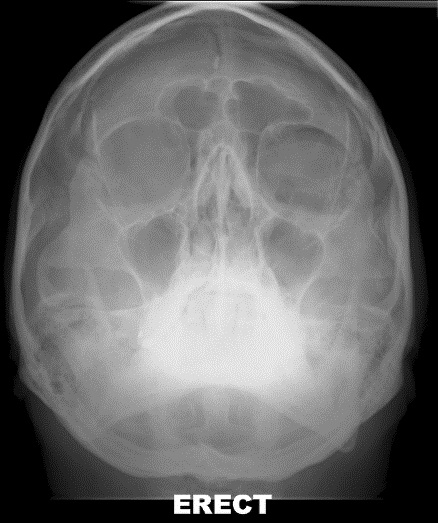

Radiograph of the black eyebrow sign[1], seen in pathologies such as Orbital Emphysema

Bickle I, Black eyebrow sign - orbital blow-out fracture. Case study, Radiopaedia.org (Accessed on 04 Jul 2024) https://doi.org/10.53347/rID-22525